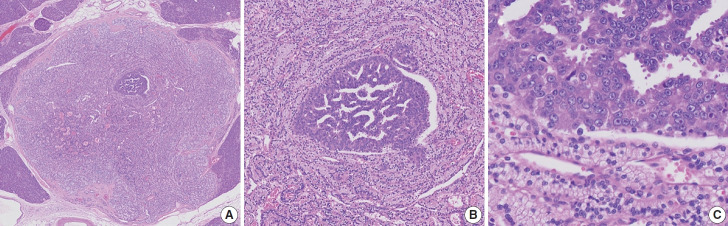

胰腺神经内分泌微瘤(PNEMT)是一种直径小于 0.5 厘米的神经内分泌肿瘤(NET),被认为是良性的。我们报告了一例伴有高级别转化(HGT)的 PNEMT。一名 60 多岁、患有 von Hippel-Lindau 综合征的男子接受了 NET 手术切除。手术中发现了第二个亚厘米结节,其形态为结节内结节。0.4 厘米的外侧结节含有透明的柱状细胞,核圆形,核小体模糊不清;0.1 厘米的内侧结节含有嗜酸性细胞,核与细胞质比率增高,核呈泡状,核小体突出。外结节和内结节的肿瘤细胞突触素和嗜铬粒蛋白均呈阳性。只有内结节的 p53 呈阳性,而外结节的碳酸酐酶 9 和波形蛋白完全呈阳性。外部和内部结节的 Ki-67 标记指数分别为 2.1%(1 级)和 44.3%(3 级)。该结节被确定为伴有 HGT 的 PNEMT。我们的研究结果表明,PNEMT不一定都是良性的,也可能发生 HGT。

Pancreatic neuroendocrine microtumor (PNEMT) is a neuroendocrine tumor (NET) < 0.5 cm in diameter, and it is considered benign. We report a PNEMT with high-grade transformation (HGT). A man in his 60s with von Hippel-Lindau syndrome underwent surgical resection of a NET. A second sub-centimeter nodule with a nodule-in-nodule pattern was discovered. The 0.4 cm outer nodule contained clear columnar cells with round nuclei and indistinct nucleoli, while the 0.1 cm inner nodule had eosinophilic cells with an increased nuclear to cytoplasmic ratio, vesicular nuclei, and prominent nucleoli. Tumor cells in the outer and inner nodules were synaptophysin and chromogranin positive. Only the inner nodule was p53 positive, while the outer nodule was exclusively positive for carbonic anhydrase 9 and vimentin. The Ki-67 labeling indices for the outer and inner nodules were 2.1% (grade 1) and 44.3% (grade 3), respectively. This nodule was determined to be a PNEMT with HGT. Our findings suggest that a PNEMT may not always be benign and can undergo HGT.